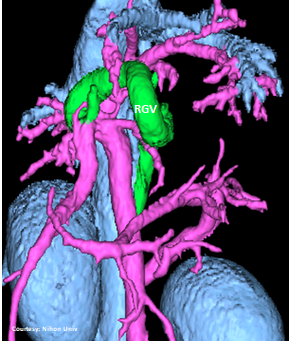

“LGC +RGV +SGV”

Left Gastro-Caval Shunt with Right Gastric Vein and Short Gastric Vein contributions

Courtesy: Nihon Univ